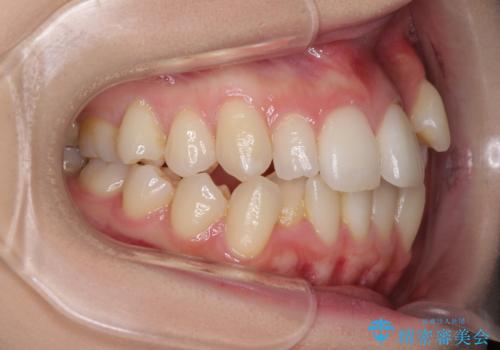

補助装置を併用したインビザラインでの八重歯の抜歯矯正

- 八重歯と奥歯の咬み合わせを気にして来院された患者様です。

インビザラインによる矯正治療を希望されたため、八重歯改善のための抜歯矯正部分は補助装置を併用し、その後はインビザラインにて行うこととしました。

下顎の右側変位が顕著であったため、ワイヤー矯正の方が咬み合わせは改善しやすいのですが、ある程度は時間がかかっても良いとのことであったので、インビザラインにて矯正治療を行うこととしました。

骨格的に下顎が右側に変位していたため、上下正中を合わせることは困難であることは分かっていました。それでも、なるべく合わせるようにとしたため、治療期間は長期間となりました。

長期間とはなりましたが、咬み合わせが改善され、患者様には大変満足していただきました。